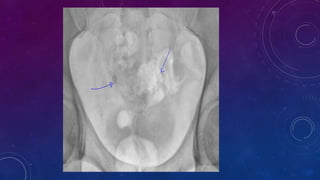

• Multiple pelvic phleboliths.

• Small well-defined round osseous lesions in the left

side of the abdomen, adjacent to midline represent

calcified lymph node in the para-aortic and left

common iliac groups, also visualized on the

corresponding CT.